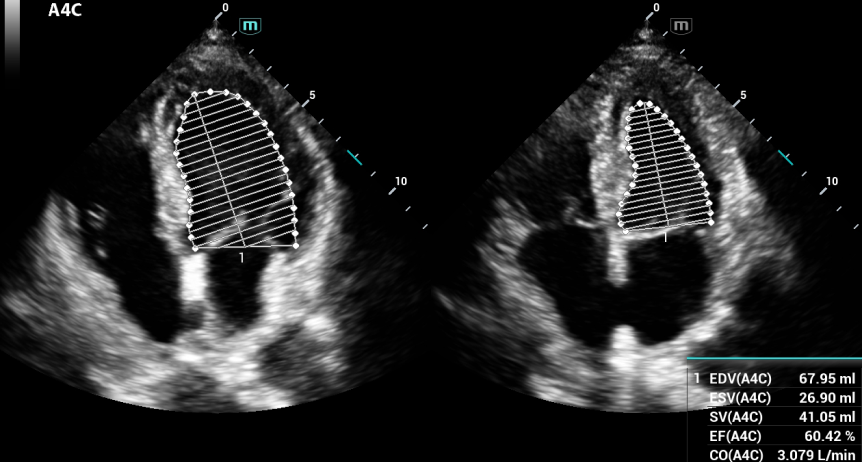

AUTO EF